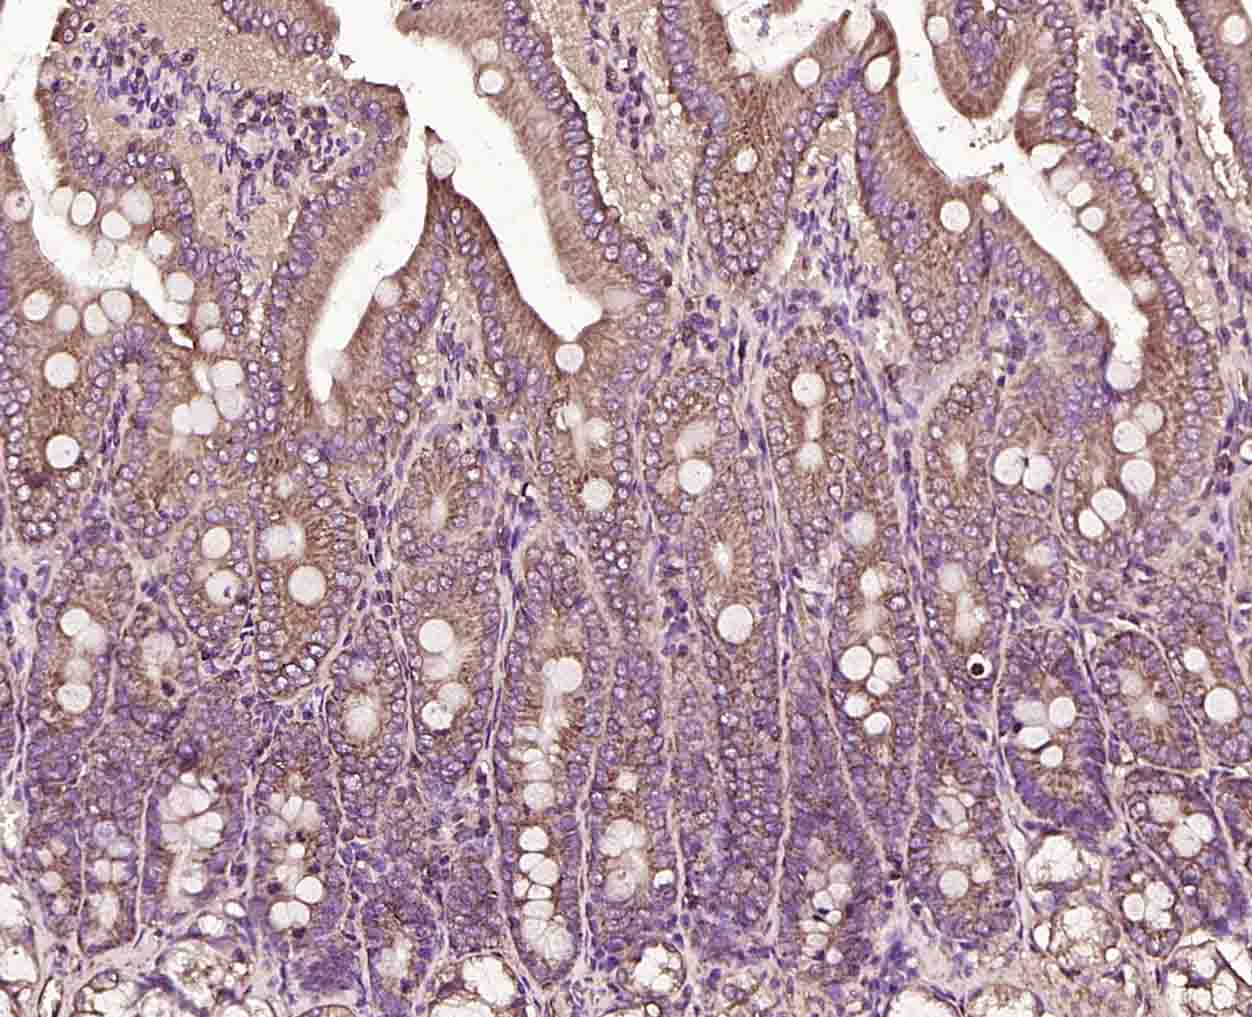

Paraformaldehyde-fixed, paraffin embedded (human liver carcinoma); Antigen retrieval by boiling in sodium citrate buffer (pH6.0) for 15min; Block endogenous peroxidase by 3% hydrogen peroxide for 20 minutes; Blocking buffer (normal goat serum) at 37°C for 30min; Incubation with (KLK4 Rabbit pAb) Polyclonal Antibody, Unconjugated (bs-2497R) at 1:200 overnight at 4°C, followed by operating according to SP Kit(Rabbit) (sp-0023) instructionsand DAB staining.

Paraformaldehyde-fixed, paraffin embedded (human lung carcinoma); Antigen retrieval by boiling in sodium citrate buffer (pH6.0) for 15min; Block endogenous peroxidase by 3% hydrogen peroxide for 20 minutes; Blocking buffer (normal goat serum) at 37°C for 30min; Incubation with (KLK4 Rabbit pAb) Polyclonal Antibody, Unconjugated (bs-2497R) at 1:200 overnight at 4°C, followed by operating according to SP Kit(Rabbit) (sp-0023) instructionsand DAB staining.

Paraformaldehyde-fixed, paraffin embedded (rat intestine); Antigen retrieval by boiling in sodium citrate buffer (pH6.0) for 15min; Block endogenous peroxidase by 3% hydrogen peroxide for 20 minutes; Blocking buffer (normal goat serum) at 37°C for 30min; Incubation with (KLK4 Rabbit pAb) Polyclonal Antibody, Unconjugated (bs-2497R) at 1:200 overnight at 4°C, followed by operating according to SP Kit(Rabbit) (sp-0023) instructionsand DAB staining.